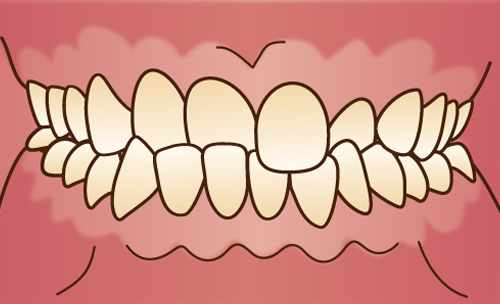

歯並びがでこぼこな乱ぐい歯、犬歯が前に突き出た八重歯などをいいます。顎が小さいと歯が生える十分なスペースがないため、歯と歯が重なり合って、叢生が生じると考えられています。